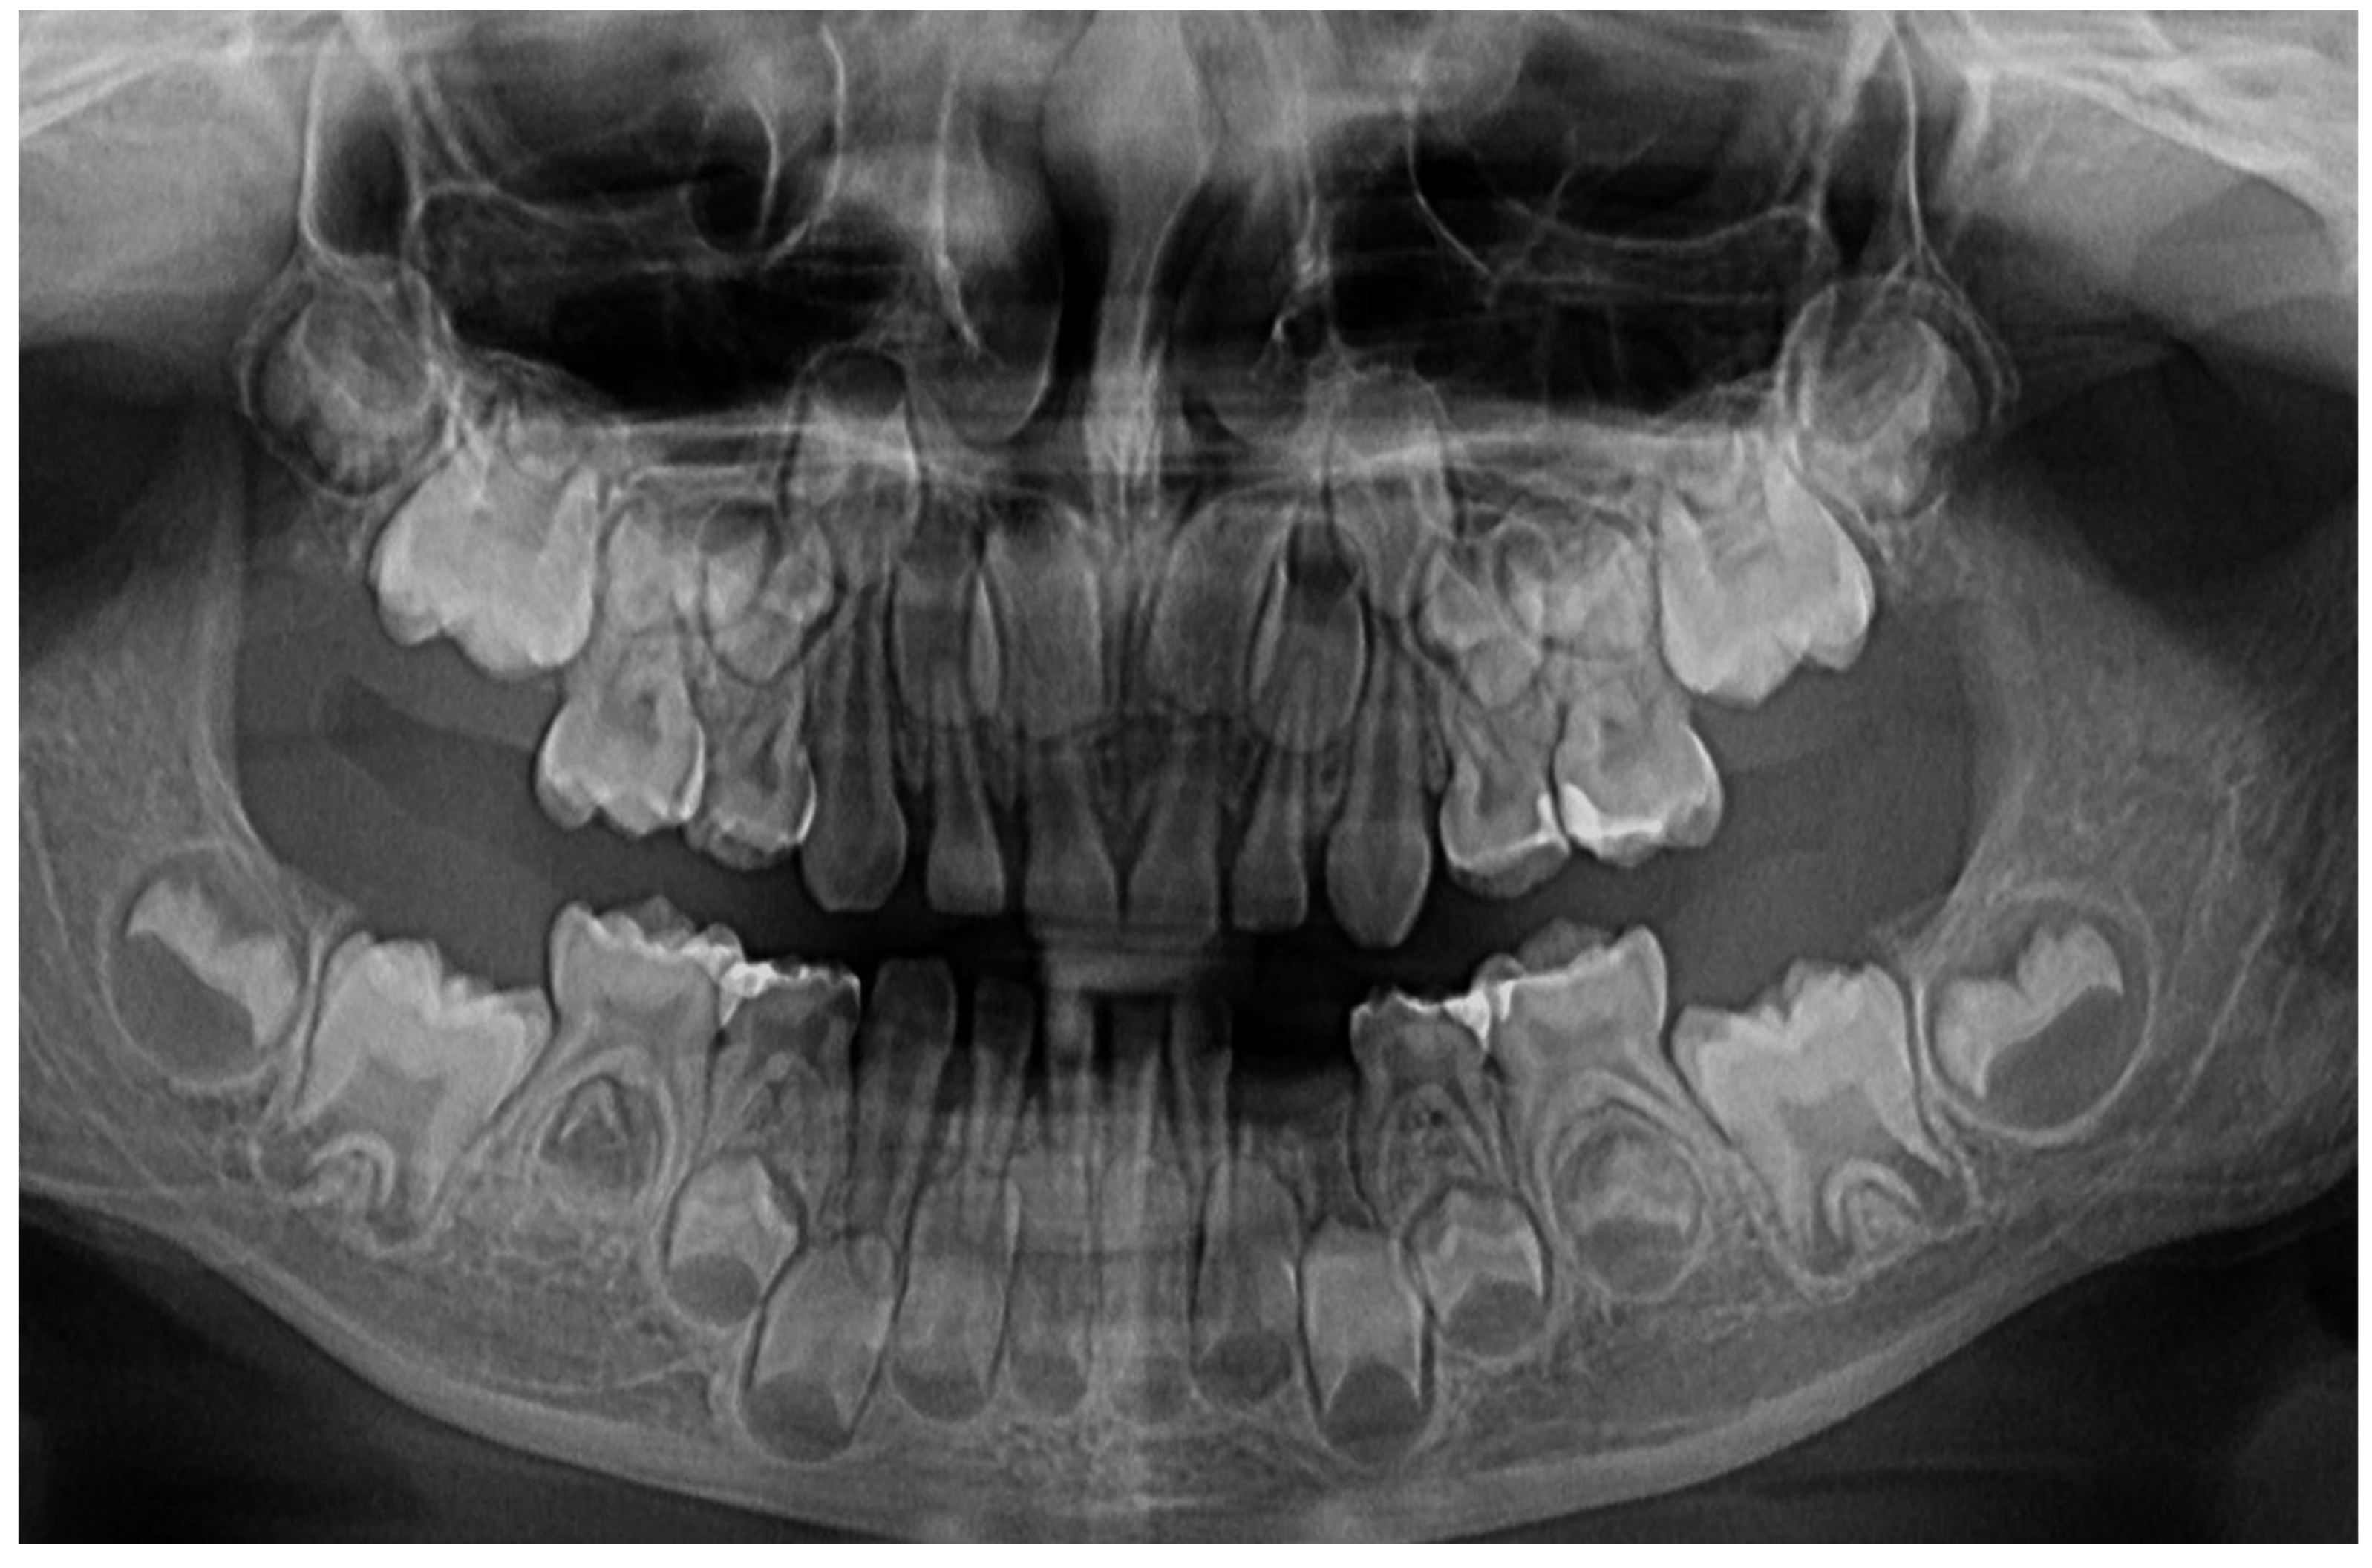

In München University Hospital (Periodontology Department, 14th of June) a full oral clinical and paraclinical examination was performed including x-ray examinations (retro-alveolar and panoramic) (Figure 1). As a result, the temporary left canine movement and a localized bone loss around the above-mentioned tooth were confirmed, with suspicion of a metabolic disease (i.e., hypophosphatasia/hyperphosphatasia) while the pain complaints were cataloged of unknown cause. No other problems were identified (e.g., orthodontic disorders, hyper-eruption, etc.). The case was dismissed with no prescribed therapy, no clinical diagnosis, and only common oral hygiene instructions. The recommendations were to continue the investigations in the Endocrinology Department for blood and genetic tests [1].

In August 2023, the family consulted another clinician abroad (2nd of August, Klausenburg/Cluj-Napoca - Romania) since parent’s concerns related to deteriorating the local conditions (inflamed periodontium around lower temporary canine and enhanced movement, Figure 2). The parents presented the entire documentation gathered from previous examinations including paraclinical tests results and x-rays [1]. After reviewing familial history and clinical and paraclinical examinations (3rd of August) the initial hypophosphatasia/hyperphosphatasia suspicions were dismissed (also confirmed by late September 2023 genetic test negative results) and the Stage IV grade C localized periodontitis/pre-puberal localized aggressive periodontitis-LPP was made. No orthodontic problems were detected during the clinical examination (also confirmed by previous clinical exams), and only the hyper-eruption of the temporary left canine due to advanced periodontal loss and surrounding inflammation (Figure 2) [1]. When setting up the LPP diagnosis, the previous x-rays (Figure 1) were taken into consideration along with girls other paraclinical results. For laboratory confirmation, a periodontopathic bacteria sample was taken (3rd of August). Since the advanced localized periodontal loss and tooth movement only professional hygiene and adjuvant topical applications with amoxicillin and metronidazole association around the inflamed periodontal pocket for a period of 10 days was prescribed. The parents were informed about all these above-mentioned issues, and the most-likely loss of the tooth but also the necessity of instituting a general antibiotic treatment and follow-up of the case. The family left Klausenburg (Romania) 5th of August. The periodontopathic bacteria test came highly positive on the 16th of August 2023 with Fusobacterium nucleatum/periodonticum and Capnocytophaga. The tooth was finally lost in early September (Figure 2) [1].

The unusualness of this case is due to several aspects. The first is related to the extremely young age of the patient (i.e., 4 years-old in February 2023, temporary dentition), with an insidious onset, and apparently no familial aggregation or history. The second aspect is related to the misdiagnose to metabolic diseases (i.e., hypophosphatasia/hyperphosphatasia) despite the initial radiographical (i.e., Figure 1) and clinical examination that suggested a clear picture of an unusual LPP (e.g., the lower left canine involvement). The third aspect is related to the lack of therapeutic measures that rapidly set the course for the periodontal and 7.3 loss, in an interval of around 7 months (Figure 2) and the further progression involving other oral sites (Figure 3 and Figure 4). The fourth aspect is related to the evolution under adequate treatment (despite no written report to guide it) and the periodontal gain over a period of around 8 months following the antibiotic therapy (Figure 5 and Figure 6).

The clinical examination as well as the complementary radiological one could point out the LPP diagnosis, despite the unusual involvement and limitation to temporary canines (the literature reports the involvement of molars and incisors) [2,3,7,8,9,10,11,12,13]. The initial “U” shape bone loss [2,3,4,5,6] and limitation to 7.3 site can easily exclude a general metabolic disease (where usually there is no such limitation). The hypophosphatasia/hyperphosphatasia misdiagnosis (i.e., June 2023) can be easily rejected since the blood count and urine test displayed no such signs (i.e., high phosphate serum levels, low levels of parathyroid hormone due to hypercalcemia and hypercalciuria) [26,27]. The initial blood test (20th of June 2023) revealed a slight increase in monocytes and lymphocytes, and a small decrease in neutrophile granulocytes, perfectly normal in case localized inflammation due to bacterial infection.

Figure 1. First x-ray radiological investigations (14th of June 2023): A – panoramic with advanced periodontal loss around lower left canine, B – retro-alveolar aspect of the 7.3 periodontal loss (München, Germany).